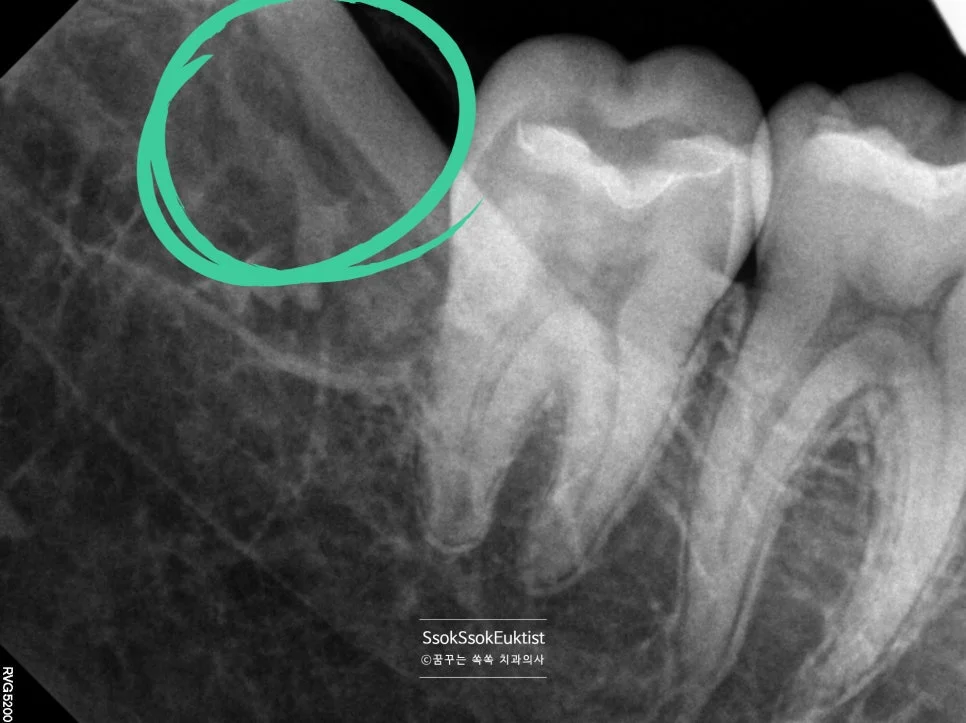

신경관 근접 매복 사랑니 엑스레이

잔존 뿌리 없이 발치가 아주 잘 된 모습이고요^^

발치 후 엑스레이 — 잔존 뿌리 없이 깨끗하게 제거